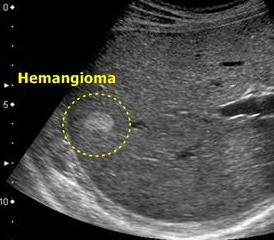

Для диагностики, подтверждающей наличие данного заболевания, применяют исследования разной направленности:

- 2) При помощи УЗИ метода хорошо видны образования с четко очерченными границами.